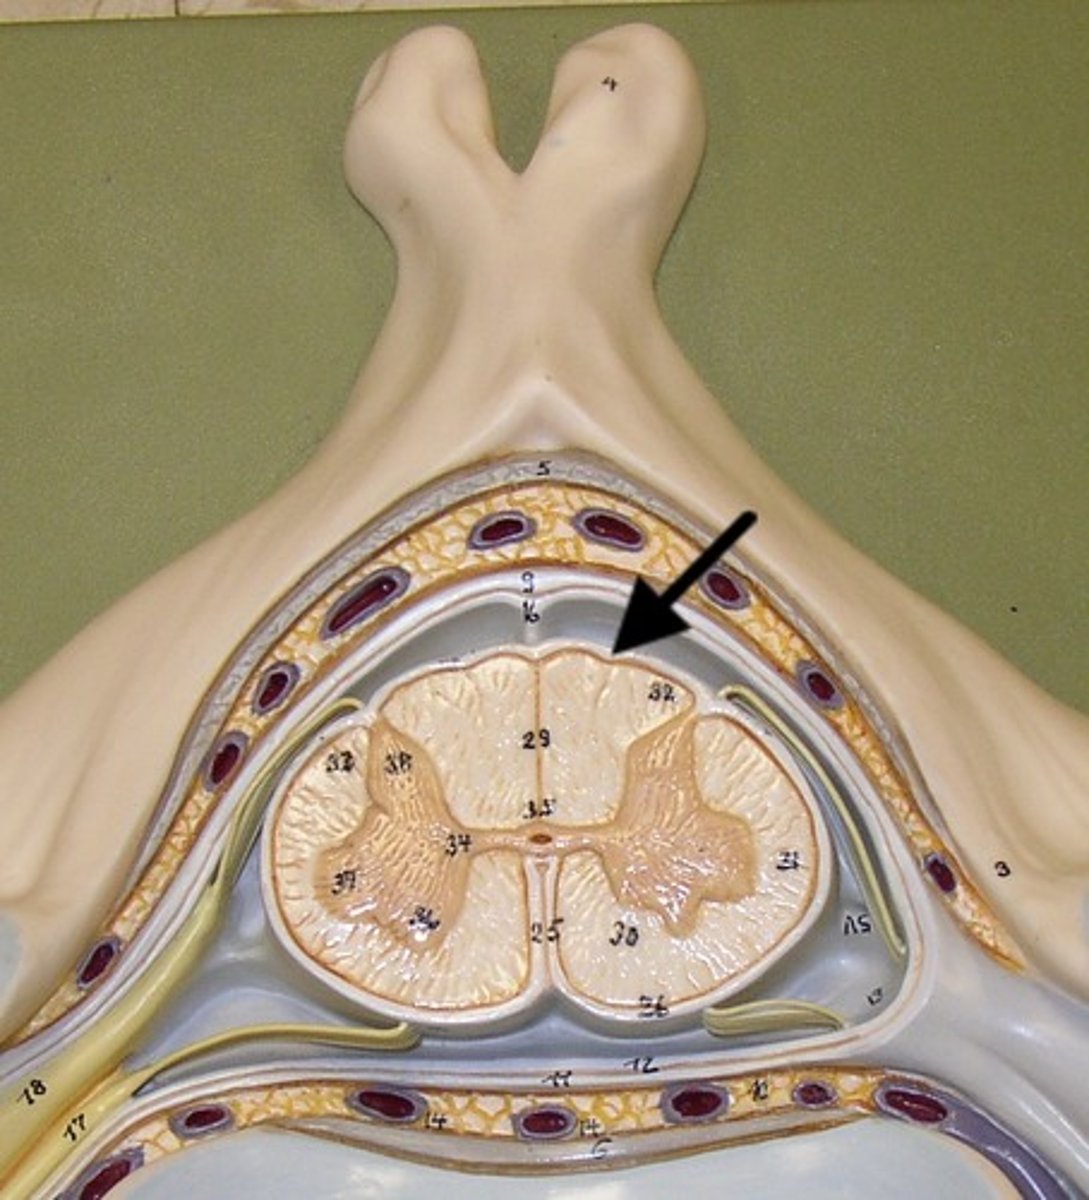

posterior root

posterior root ganglion

2

anterior root

1

3

posterior ramus

4

anterior ramus

5